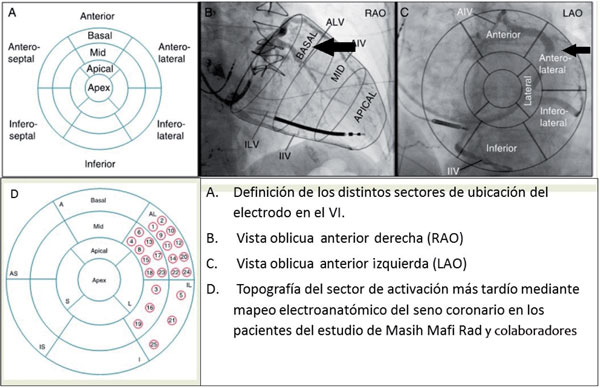

La ubicación del electrodo en la pared anterior y en la zona apical del VI es la que conlleva la peor respuesta a la TRC39(Figura 3).

Figura 3: Definición de los distintos sectores de ubicación del electrodo en el VI y su visualización según los enfoques (A, B, C) y resultados del mapeo en pacientes del estudio de Masih Mafi Rad (D). Modificado de referencia 39.

Se ha evaluado la utilidad de los estudios de medicina nuclear (análisis de fase en el SPECT), ecocardiográficos (speckle tracking) y con sistema de mapeo tridimensional para ubicar el sitio de activación más tardía para decidir la implantación del electrodo del VI. Si bien hay algunos resultados alentadores, todavía no han logrado relevancia clínica, por lo que se necesitan estudios randomizados de mayor porte para generalizar su uso39.

- El lugar de ubicación del electrodo puede influir en el resultado de la TRC, siendo los sectores lateral y posterolateral basal los más eficaces.